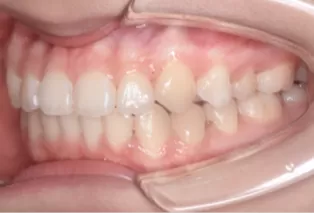

Photos intra-orales